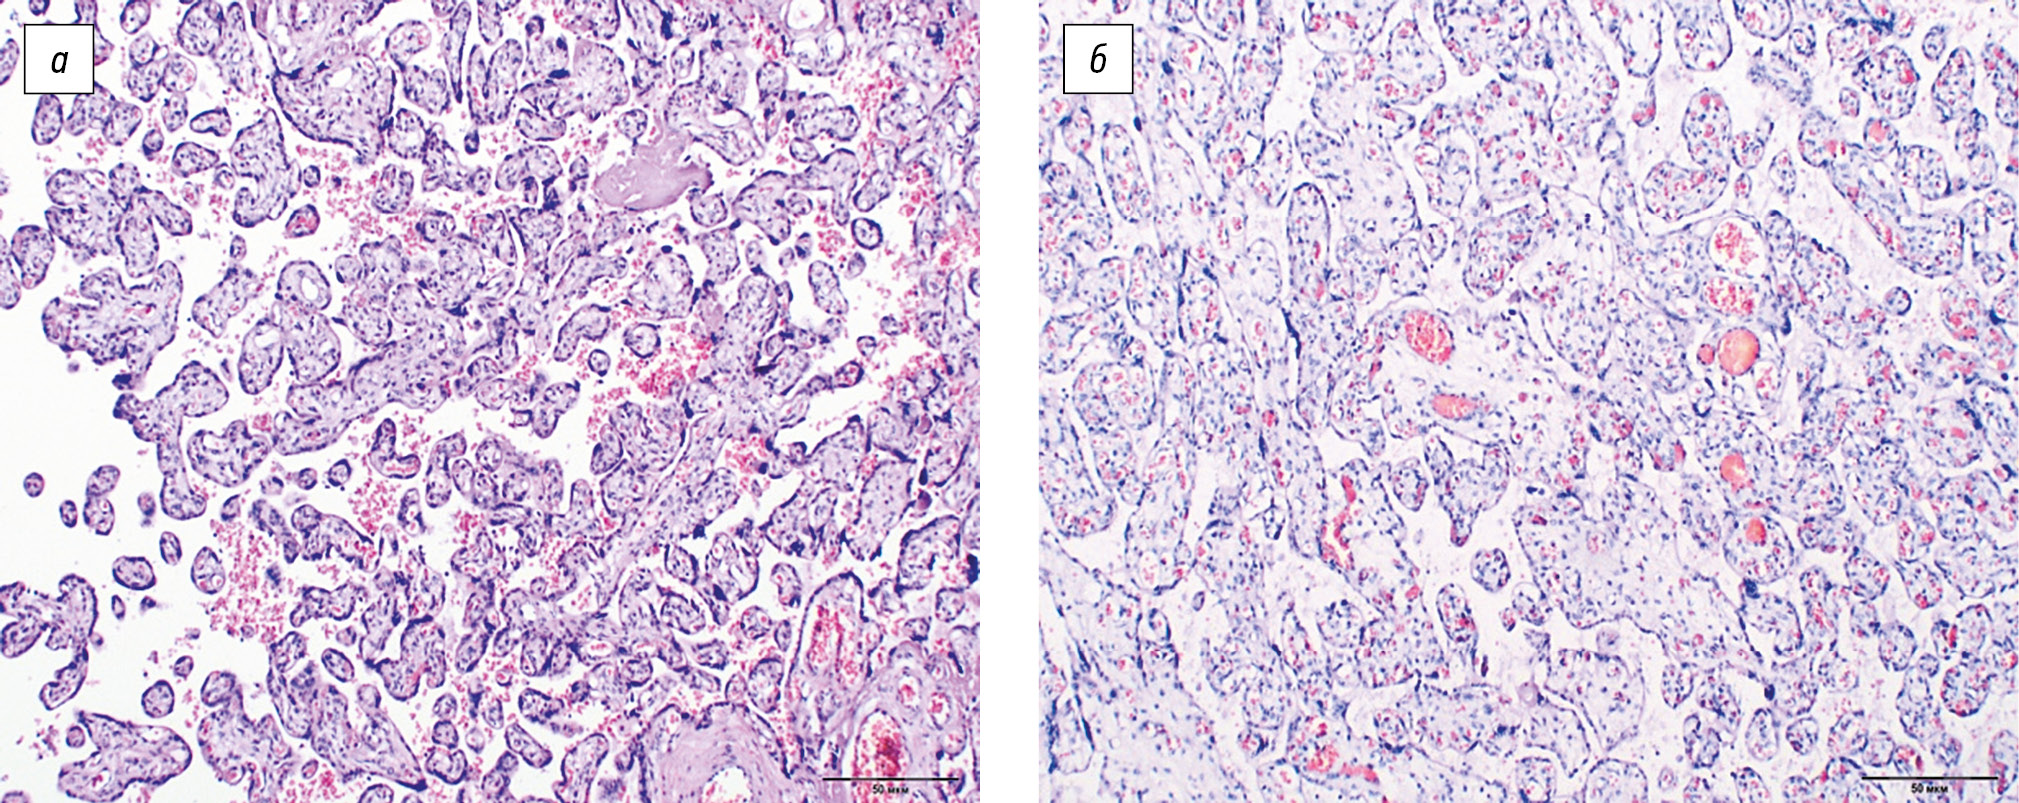

Inflammatory changes in the placenta in group 1 are represented by hematogenous infection in 18.2% (4) and signs of ascending bacterial infection in 81.8% (18) of cases. Hence, hematogenous infection of the placenta was characterized by stromal hypercellularity with monocytic infiltration (productive villusitis) in three (75%) placentas. Dystrophic and desquamative changes in the chorial epithelium with perifocal fibrinoid deposition (fibrinous-desquamative intervillositis) were detected in one (25%) case (Fig. 2).

Fig. 2. Hematogenous infection of the placenta: (a) desquamative-dystrophic changes in the chorial epithelium with perifocal deposition of fibrinoid masses and lymphoid infiltration (staining with hematoxylin and eosin, ×100); (b) fibrinous-desquamative intervillositis (staining with hematoxylin and eosin, ×200)